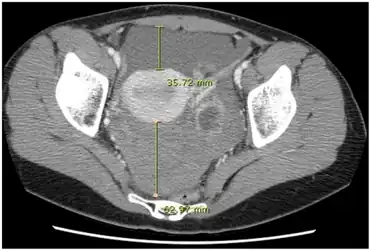

CT quantification of hemoperitoneum.